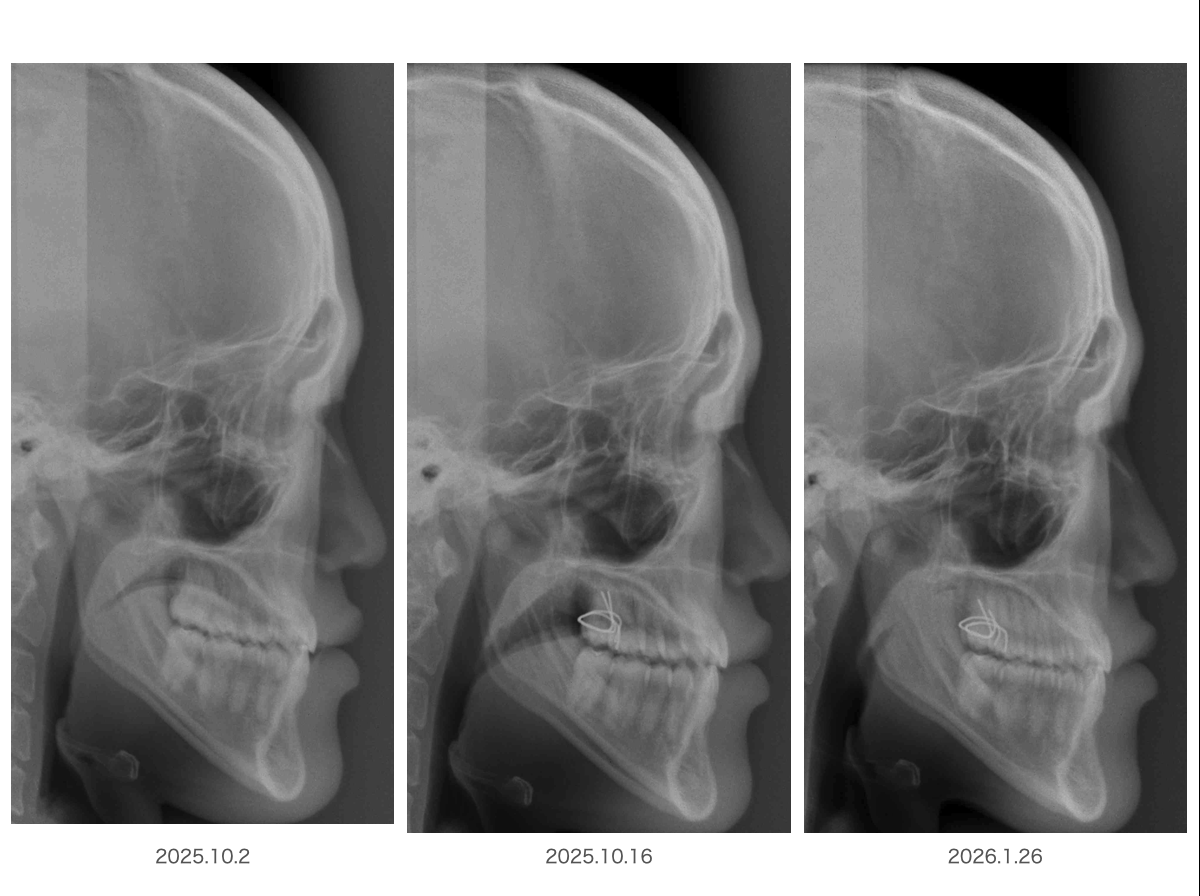

ここに3枚のレントゲンがありますが、もちろん同一人物であり、昨年10月2日からの変化になります

よく見比べてみて何が違うのか探してみてください・・・・

例えば画像を拡大してみたり。。。。

咽頭部を拡大してみたらいかがでしょう?

顎が前に出たからなのでしょうか?

実はこの顎が前に出る反応もご本人の意思とは関係なく反射的に起こっています